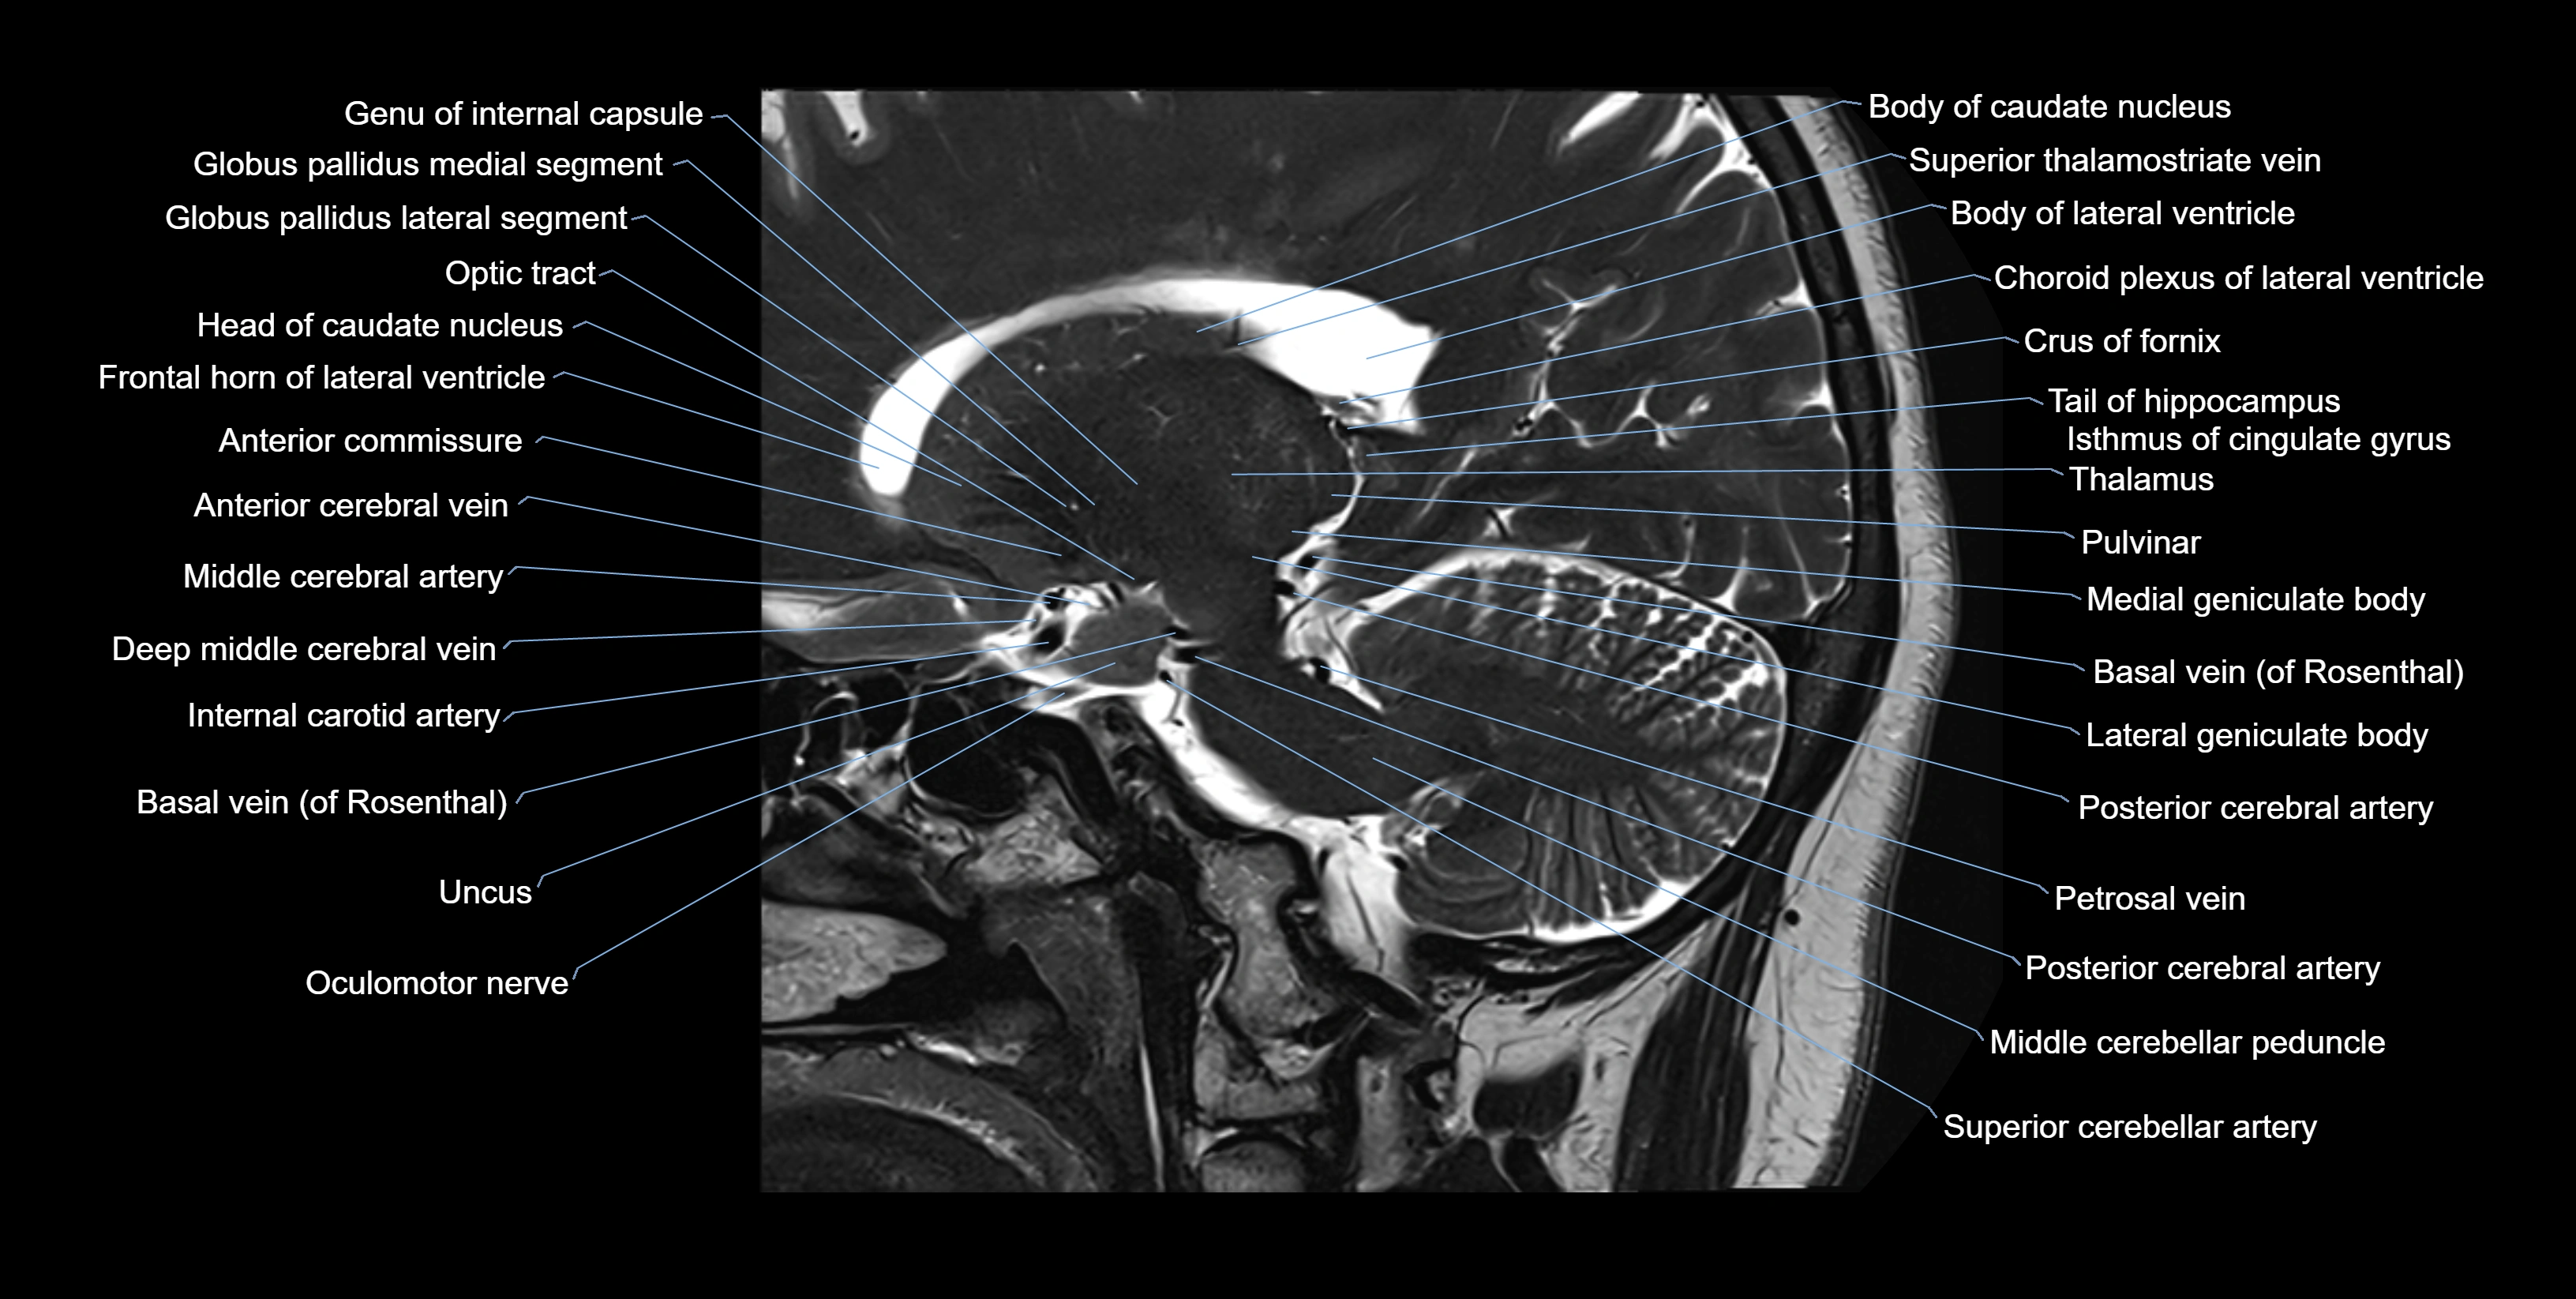

The alveus of the hippocampus is a thin, white matter layer covering the superior (ventricular) surface of the hippocampus within the temporal horn of the lateral ventricle. It consists of myelinated efferent fibers arising primarily from the pyramidal neurons of the hippocampus. These fibers converge medially to form the fimbria of the hippocampus, which continues posteriorly into the fornix, forming a crucial part of the Papez circuit involved in memory consolidation and emotional processing.

The alveus serves as the initial output pathway of the hippocampal formation, linking it to other limbic structures including the hypothalamus, mammillary bodies, and cingulate gyrus. Because of its intimate relationship with the hippocampal head and tail, it is often evaluated in cases of temporal lobe epilepsy, hippocampal sclerosis, and neurodegenerative diseases.

Location and Structure

• Position: Lies on the ventricular (superior) surface of the hippocampus, beneath the ependyma of the inferior horn of the lateral ventricle.

• Composition: A thin sheet of myelinated axons derived mainly from hippocampal pyramidal cells.

• Course: Fibers run medially along the hippocampal surface to form the fimbria of the hippocampus, which curves upward and backward into the fornix.

• Relations:

• Superiorly: Ependyma and CSF of the temporal horn of the lateral ventricle

• Inferiorly: Pyramidal cell layer of the hippocampus (CA1 region)

• Medially: Fimbria and fornix

• Laterally: Temporal lobe white matter and parahippocampal gyrus